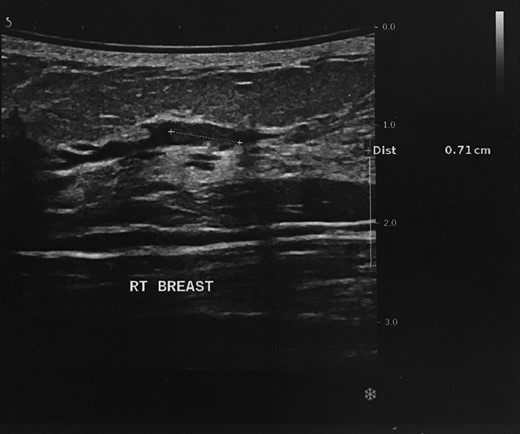

Ultrasound revealed that the well-circumscribed mass was a simple cyst; however, there was an additional hypoechoic solid mass of 0.7 cm in maximum diameter within a single dilated duct, compatible with an intraductal papilloma (Fig. 2). Axillary lymph nodes were benign. The mass was graded as 4 on the BIRADS (Breast Imaging Reporting and Data System) scale.